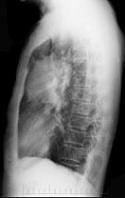

- 单项选择题女性,51岁, 胸痛数月,痰血两天, X线检查见图,最可能的诊断是 ( )

A、左肺癌

B、左侧炎性假瘤

C、左侧纵隔肿瘤

D、左肺转移瘤

E、支气管扩张